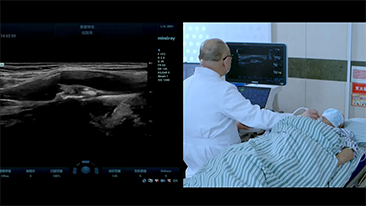

Mindray Resona General Imaging solutions help clinicians realize more accurate and efficient diagnosis and treatment results through comprehensive subdivision application probes and efficient clinical application tools.

General Imaging Products